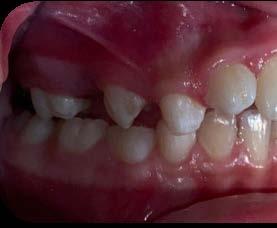

Entre los elementos que conforman al sistema estomatognático, están los dientes caninos, órganos dentales esenciales en la fisiología masticatoria; punto de unión y continuidad estética entre la línea de la sonrisa y el corredor posterior del arco dental, además de que ejercen la función de pilares estabilizadores en la oclusión fisiológica (Figura 1).

Los caninos son indispensables durante los movimientos de lateralidad y vitales para la continuidad de los arcos dentales, tanto en la dentición decidua como en la permanente; son responsables del funcionamiento y la armonía oclusal. Su posición adecuada en el arco asegura un buen contorno de la cara, sonrisa agradable y armónica con la estética facial. (Figura 2).

El canino divide su cara vestibular en 2 vertientes, una mesial que se continúa con los incisivos y otra distal que se alinea con los dientes posteriores, razón por la cual su ausencia genera alteraciones muy importantes en la oclusión y la estabilidad fisiológica del sistema estomatognático (Figura 3).